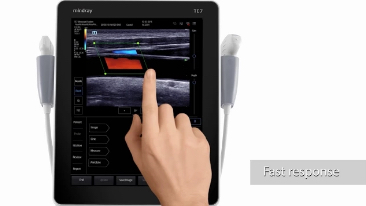

With its superior image quality, simple touchscreen operation and class-leading intelligent tools, the Mindray TE7 ACE is designed to simplify and speed-up ultrasound examinations.

Its versatility makes it suitable for demanding point-of-care environments including Critical Care, Emergency and Anaesthetics.